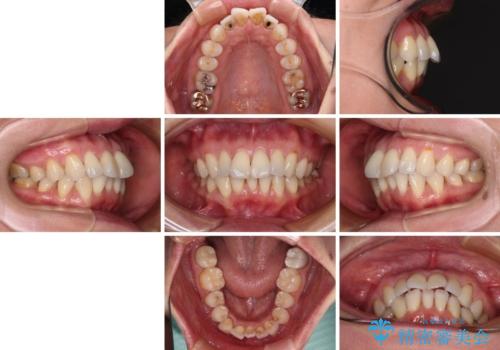

前方に飛び出した前歯 ワイヤー装置での抜歯矯正

- 前方に飛び出した前歯を気にして来院された患者様です。

通常であれば上下左右の第一小臼歯4本を抜歯して口元の突出感を改善しますが、下顎前歯が1本欠損しており、上下の歯の数がアンバランスであるため、4本抜歯するかどうか悩むところでした。

上顎前歯はやや小さめで、下顎前歯はやや大きめであったため、上下左右4本を抜歯しても左右奥歯の咬み合わせは理想に近い状態を達成できると判断し、上下左右の第一小臼歯4本を抜歯し、ワイヤー装置にて矯正治療を行うこととしました。